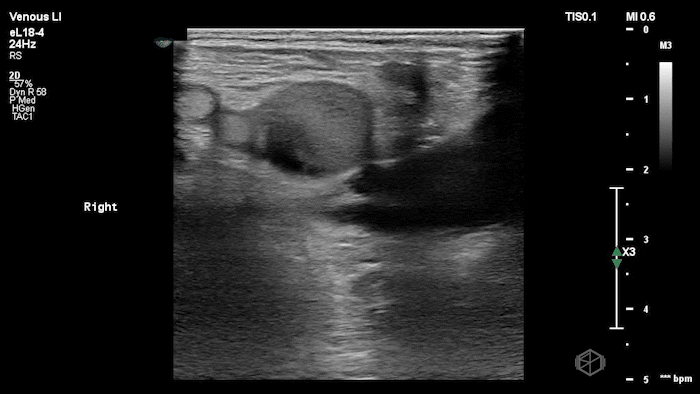

03 - What is the diagnosis and what other procedure was the patient undergoing?

Non-occlusive DVT; patient was simultaneously getting a contrast echocardiogram. The whitish flow is due to ultrasound contrast.